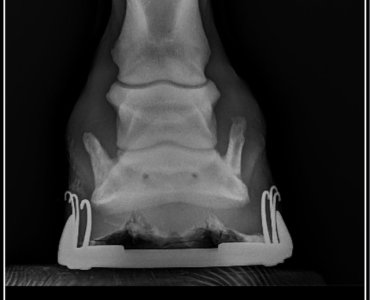

Anyway, part of the X-rays he got done was his front feet which didn’t show anything other than side bone. The vet wasn’t concerned and neither was my farrier today but he did say it explained a lot about his feet.

I’ll attach screenshots of the x-rays if anyone is interested!